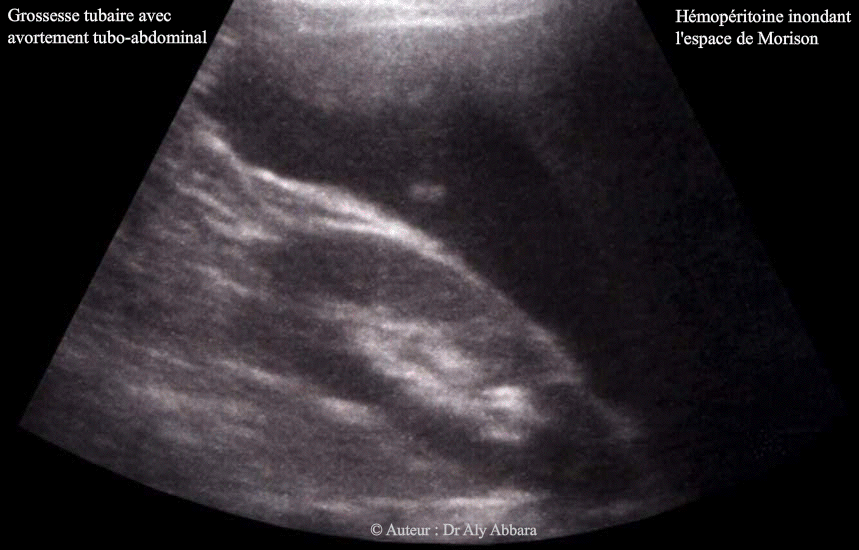

Espace de Morrison - Inondation péritonéale suite à une rupture d'une grossesse extra-utérine tubaire

• Images échographiques montrant un hémopéritoine sévère (estimé chirurgicalement à environ 1200 cc du sang) avec une inondation de l'espace de Morrison (l'espace interhépatorénal) ; cet hémopéritoine était provoqué par un avortement tubo-abdominal incomplet d'une grossesse extra-utérine tubaire distale (ampullaire) gauche se manifestant par la survenue brutale d'une douleur abdominale localisée, au début, dans la fosse iliaque gauche, puis généralisée dans la totalité de l'abdomen, avec la progression rapide vers un état de choc hémorragique.

• L'espace de Morrison fait partie des régions à explorer échographiquement devant tout cas de suspicion de grossesse extra-utérine ou d'hémorragie intra-péritonéale.